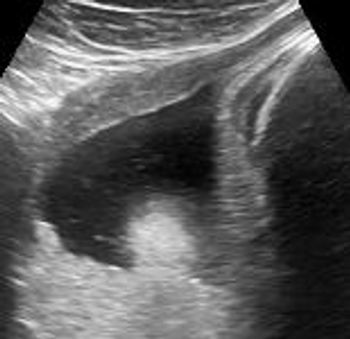

QUIZ: What's causing the compression of the fetal heart (tubular shaped), ascites and dilated trachea?